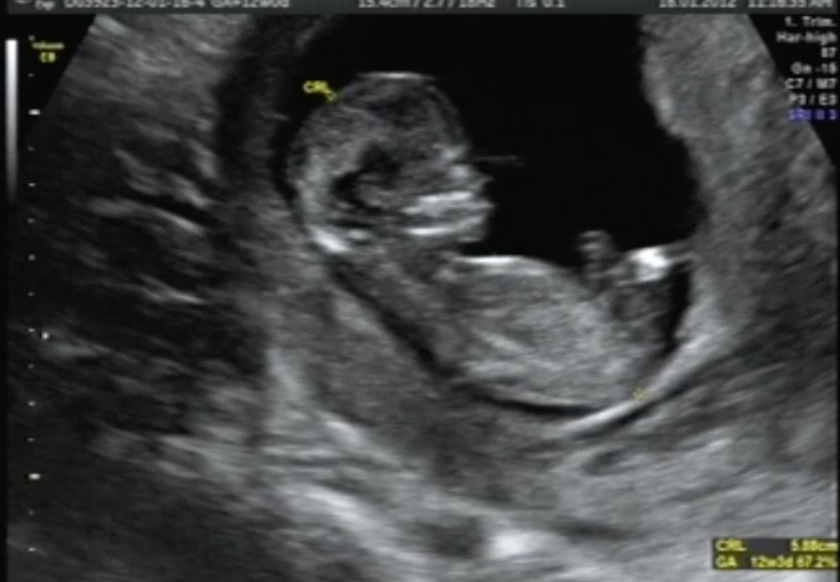

Είναι η στιγμή που κάθε έγκυος γυναίκα περιμένει με λαχτάρα: Να αισθανθεί για πρώτη φορά τις κινήσεις του μωρού στην κοιλιά της. Αρχικά νιώθεις κάτι σας γουργούρισμα και μέρες αργότερα συνειδητοποιείς πως πρόκειται για τις μικροσκοπικές ”κλοτσιές” του μωρού σου. Πως όμως αισθάνεται το μωρό τις κινήσεις της μαμάς του; Τι παθαίνει όταν η μαμά του γελάει, έχει λόξιγκα ή φτερνίζεται; Όπως εξηγεί η γυναικολόγος Δρ Τζάνετ Ντι Πιέτρο από το ερευνητικό Πανεπιστήμιο Johns Hopkins στη Βαλτιμόρη των ΗΠΑ, δεν υπάρχει κανένας λόγος ανησυχίας. ”Τόσο ο μυικός ιστός της μήτρας, όσο και τα αμνιακά υγρά προστατεύουν απόλυτα το μωρό στα σπλάχνα μας, μιας και το μόνο αισθάνεται όταν γελάμε ή φτερνιζόμαστε είναι ένα ελαφρύ τράνταγμα, σαν να κάνει.. τραμπολίνο. Την επόμενη φορά που θα πάτε στο γυναικολόγο σας για να κάνετε τον προγραμματισμένο υπέρηχο, βρείτε μια καλή αφορμή για να γελάστε και θα το διαπιστώσετε.. από πρώτο χέρι”. Δείτε το βίντεο που ακολουθεί: